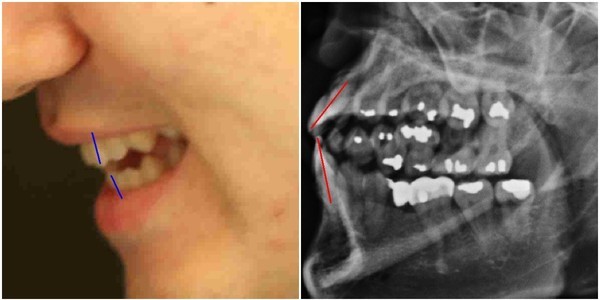

김우현씨는 박주신씨가 자생병원에서 MRI를 촬영하면서 함께 찍은 엑스레이 사진에 의문을 나타냈다.

박주신씨의 치아가 보이는 ‘구외 엑스레이’(이하 치아 엑스레이) 사진에서 나타나는 피사체의 치아상태는 불량하기 짝이 없었다.

도저히 중산층 가정의 20대 청년의 것으로 볼 수 없을 만큼 치아상태가 나빴다.

- ▲ 박주신씨 명의의 치아 엑스레이 사진. ⓒ 뉴데일리DB

김우현씨는 서울 방배동에 살던 20대 청년이 무려 14개에 이르는 치아를 아말감으로 치료 하고, 일부 치아는 아예 빠진 채 몇 년간 방치된 사실에 고개를 가로저었다.

아말감은 수은증기 논란과 변색의 문제점 등으로 1990년대 들어 사용빈도가 급감했다. 2005년경 서울의 중산층 청년이 하나도 아닌 무려 14개의 치아를 아말감으로 치료한다는 것은 상식 밖이었다.

김우현씨는 치과의사로서의 임상경험을 근거로, 자생병원 엑스레이 피사체의 정체에 의문을 가졌다.